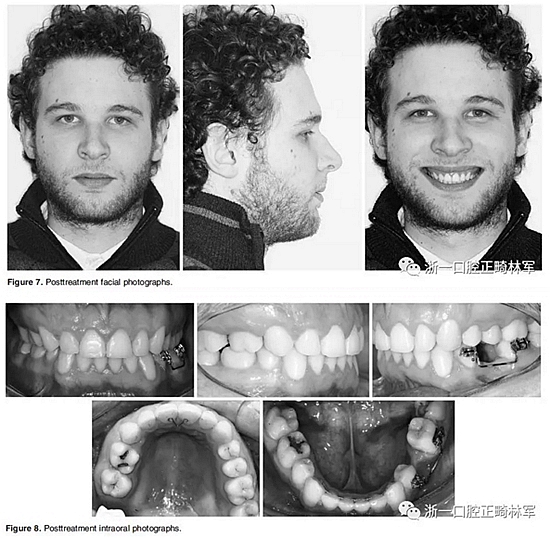

在治療結(jié)束時(shí),面部基本對(duì)稱(Figure 7)。上中線與面中線重合,下中線向左偏0.5mm,傾斜的合平面得到矯正,獲得了良好的咬合關(guān)系,具有正常的覆合和覆蓋,留下7mm的空間用于植入左下前磨牙(Figure 8、9)。